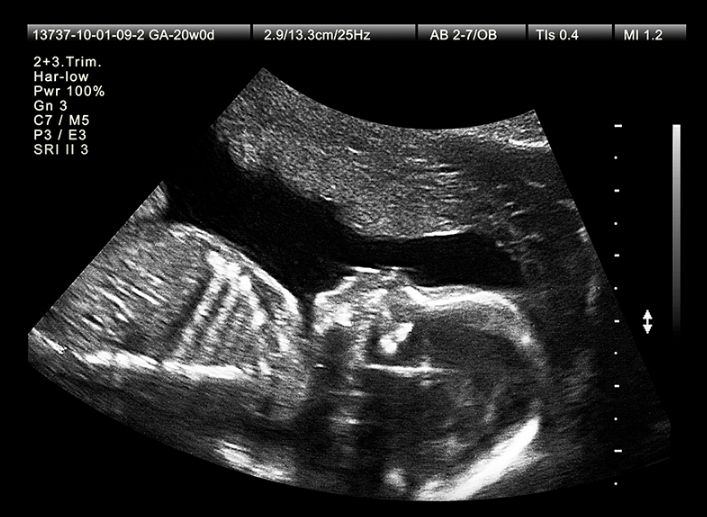

Siêu âm 2D hiện là phương pháp chẩn đoán hình ảnh được dùng phổ biến nhất ở các cơ sở y tế để theo dõi thai kỳ. Đây là phương pháp siêu âm thai ở mức độ 1, tuy lâu đời nhưng vẫn được áp dụng trong khám thai cũng như theo dõi ổ bụng, tim mạch.

Siêu âm 2D là phương pháp siêu âm truyền thống với kết quả mang lại hình ảnh có màu đen trắng, có cùng mức độ như một phim âm bản. Tuy nhiên, siêu âm 2D không hề thua kém với các dạng siêu âm hiện đại như 3D hay 4D. Vì phương pháp siêu âm này vẫn cung cấp đầy đủ các thông tin cần thiết của thai nhi như: Tình trạng phát triển của thai nhi, tuổi thai, độ dài, kích thước thai, các dị tật bẩm sinh nếu có và nước ối, nhau thai, cấu trúc tử cung. Đặc biệt, siêu âm 2D hoàn toàn có thể xác định được cân nặng của thai nhi nhằm theo dõi, đánh giá sự phát triển của thai nhi.